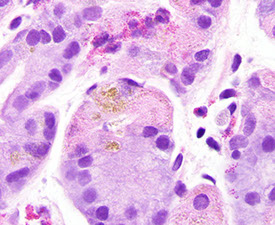

Iatrogenic injury / Chemical injury

Iron

Relatively common; usually in concert c some other dz process

- can have iron thrombi; has similar appearance as iron esophagitis

- may have severe changes that mimics carcinoma

- systemic iron overload (siderosis) is more rare and may cause changes in deep gastric glands

Iron pill gastritis with severe reactive epithelial changes [1]

gastric siderosis [1]

Gastric siderosis, iron stain [1]